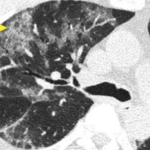

Radiologic Sign of the Day (CT) for COVID: Crazy Paving

On cross sectional CT imaging of the lung, sometimes, you might see what is known as thickened interlobular and intralobular lines (opacities)...